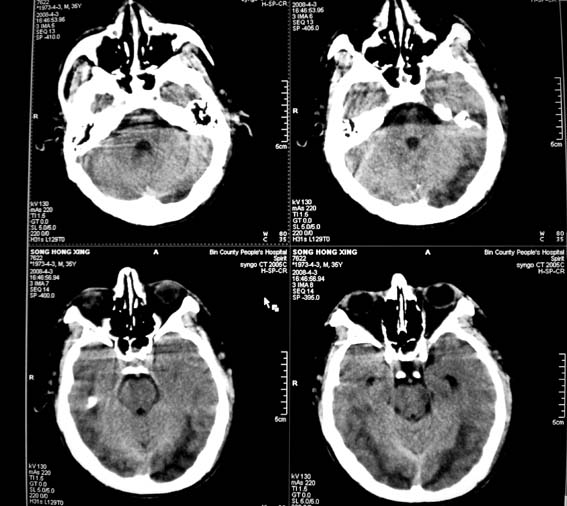

标题: CT12659:头外伤,现昏迷。 [打印本页]

标题: CT12659:头外伤,现昏迷。

10天前,头、胸、腹及腿部外伤,当时有蛛网膜下腔出血,肺挫伤,肝脾破裂,腿部骨折,近两天昏迷。

sah,dai,双枕顶叶外伤性脑梗死。dai的受伤机制是脑的瞬间旋转作用和脑内剪切力所致。临床表现为昏迷出现早,昏迷程度深,昏迷持续时间长,恢复不完全。ct表现为脑白质区散在的局灶出血点,颅内高压表现不明显。